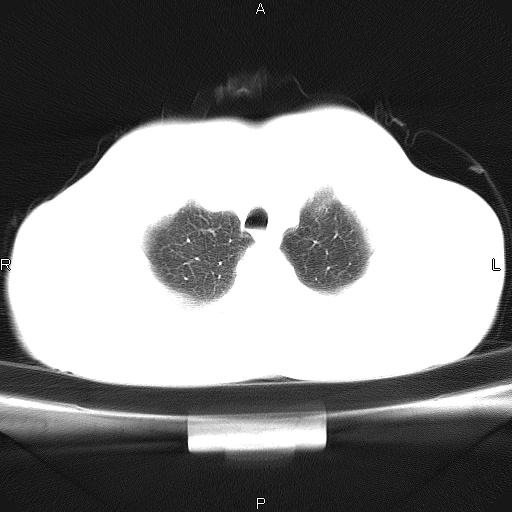

左下肺片状高密度影,境界模糊,密度不均,考虑感染性病变可能性大,建议抗炎治疗后复查。左肺门增大,不除外占位性病变,必要时支气管镜检。

考虑感染性病变可能性大,抗炎后复查,占位不排除。

建议强化或纤支镜观察,考虑肿瘤性病变可能性大